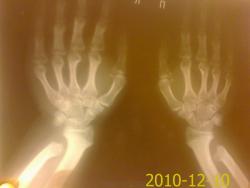

рентген кистей

Какая-то дисплазия?

У Рейнберга нашла похожую картинку, у него это хондродистрофия (ахондроплазия).

Если не ошибаюсь, укорочение локтевой кости с деформацией лучезапястного сустава называется аномалией Маделунга, и наоборот, укорочение лучевой кости Антимаделунга. Но в данном случае ещё отмечается какое-то укорочение пястных костей, что похоже на сочетание с хондродисплазией.

http://www.radiomed.ru/cases/bolezn-madelunga      и      http://www.radiomed.ru/publications/kss-klassifikatsiia-displazii-skielieta-iz-knighi-ig-laghunovoi-kliniko#comment-8272    -  согласитесь, разница есть. Наверное, Ola-la права (вместе с Рейнбергомsmiley, на картинках и укорочение пястных костей тоже), и тут "чистая" хондродистрофия. Спасибо за случай!